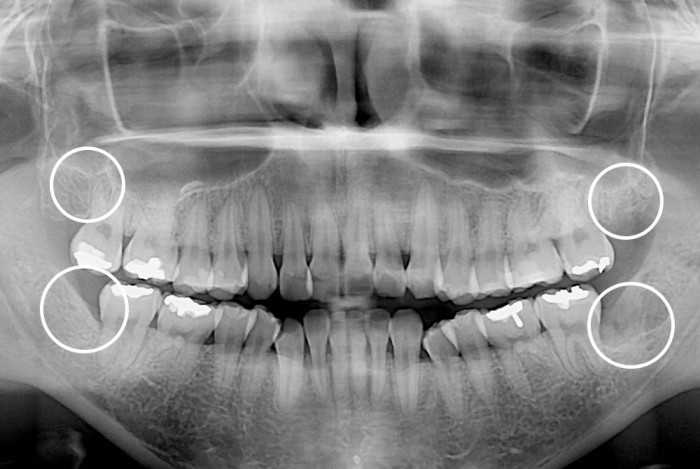

[사랑니] 사랑니

치료전 : 2015-02-24

세종치과는 구강악안면외과학 박사이신 원장님이 발치하는 치과입니다.